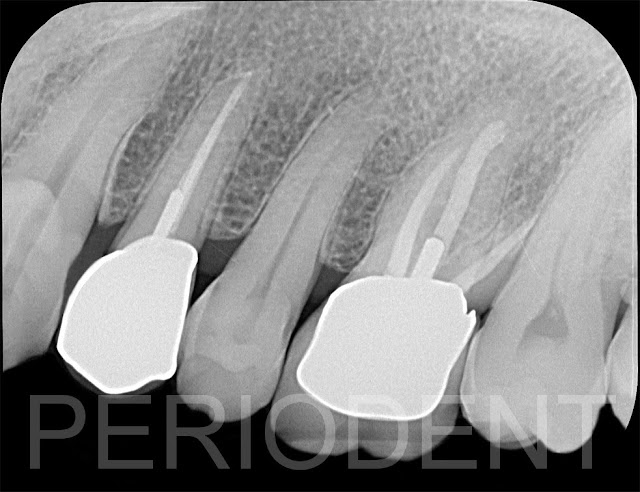

患者第一小臼齒遠心蛀牙

先進行根管治療

三個月後裝上正式假牙